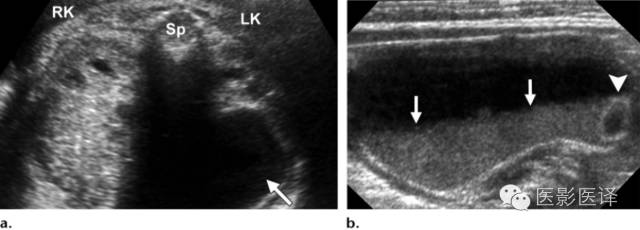

图7 囊肿中的液液平面。(a)轴位胎儿超声图像显示在左肾(LK)前方一个孤立性囊性肿块(箭),脊柱(Sp)另一侧可以看到正常的右肾(RK),三周后的随访图像(未展示)显示团块中出现液液平面。(b)新生儿经腹长轴位图像显示一个薄壁囊性团块,有液液平面(箭),子囊(箭头)是卵巢囊肿的确诊征象。(c)新生儿矢状位T2WI显示一个出血性卵巢囊肿,有液液平面(箭)和低信号血液成分。